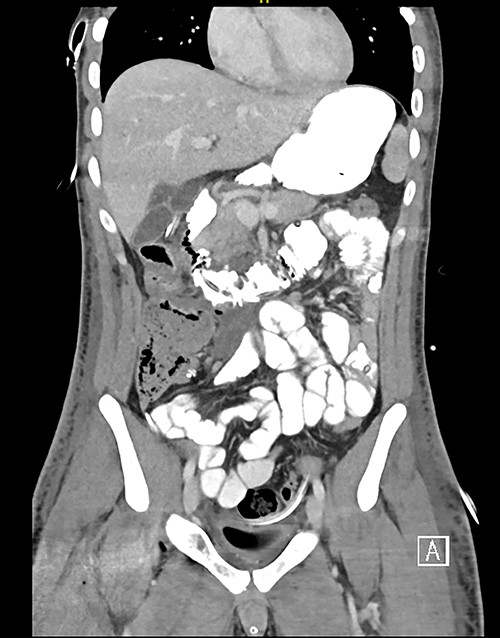

Here, we report a case of a 21-year-old man who was admitted to our hospital following a motor vehicle collision where he was a pedestrian, hit by a car and pushed against the bumper of another car. Upon arrival to the hospital, he was conscious and oriented, with normal vital signs. Abdominal examination revealed ecchymosis over the epigastric area with tenderness, however, no distention was noticed. Focused assessment with sonography for trauma result was positive in the right upper quadrant. His initial blood test results revealed a white blood cell (WBC) count of 26.5 × 109 cells/l and a hemoglobin level of 150 g/l. His serum amylase and lactic acid levels were 92 U/l and 4.53 mmol/l, respectively. His base deficit was 4.3. He underwent abdominal computed tomography (CT) with oral contrast, which showed query duodenal and possible pancreatic transection with active arterial extravasation (Figs 1–3). In addition, CT revealed a comminuted right intertrochanteric femoral fracture without associated vascular injury.

Despite its limitations in distinguishing between duodenal hematoma and duodenal perforation, CT with intravenous and intraluminal contrast remains the gold standard diagnostic test in stable patients with blunt abdominal trauma [1]. In the reported case, CT revealed duodenal and possible pancreatic transection with active arterial extravasation.